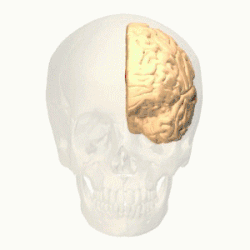

Prefrontal cortex

_animation.gif)

The prefrontal cortex (PFC) is responsible for complex cognitive behaviour, decision making and consciousness (Burton, Westen, Kowalski, & Westen, 2015). While there is still much debate as to what specific role the different areas of the PFC play in anxiety related disorders, a review conducted by Spalding in 2018, investigated the role that the medial prefrontal cortex (mPFC) has in relation to fear generalisation - conditioned fear generalising to related stimuli, (Spalding, 2018). The study found that in human subjects, the ventral mPFC plays an important role in inhibiting the fear generalisation, while dorsal mPFC is seen to activate fear generalisation. Studies indicate that "higher levels of anxiety have been associated with increased activity in the dorsal mPFC (Straube et al., 2009), but further research needs to be done to investigate this.